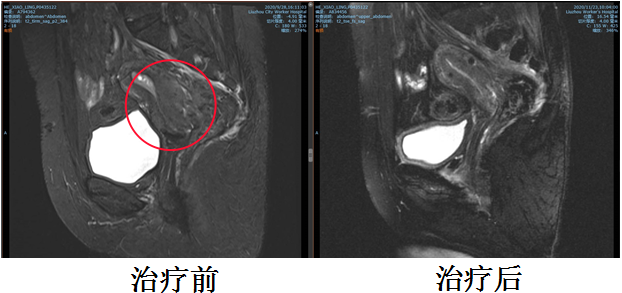

柳州市工人医院肿瘤诊疗中心腹部盆腔肿瘤一、二病区近日收治了一名宫颈鳞癌IIIB期患者,宫颈肿瘤巨大(6.2*5.4cm),侵犯右侧盆壁、左侧宫旁和膀胱后壁,已在外院行外照射放疗,就诊肿瘤诊疗中心腹部盆腔肿瘤一、二病区拟后装治疗以完成整个放疗疗程。

考虑到患者肿瘤大侵犯广泛,膀胱和盆腔侧壁高位侵犯,外照射结束后宫颈及双侧宫旁盆壁仍有明显肿瘤残留,因后装治疗进针路径通常为阴道,插值难度较大,较难布针布源满意达到合适的放疗剂量分布,同时患者对疼痛非常敏感,对后装治疗很抗拒。经治疗小组讨论后,与患者及家属沟通,拟予患者实施人工智能3D打印模板引导三维无痛插值后装治疗,鉴于是无痛和精准的治疗,患者和家属考虑愿意接受。

后予患者行定位CT扫描,调整插值针位置深度,实时勾画三维后装靶区,放疗物理师制定出放疗计划,验证计划核查无误后,后装技师开始实施后装放疗。